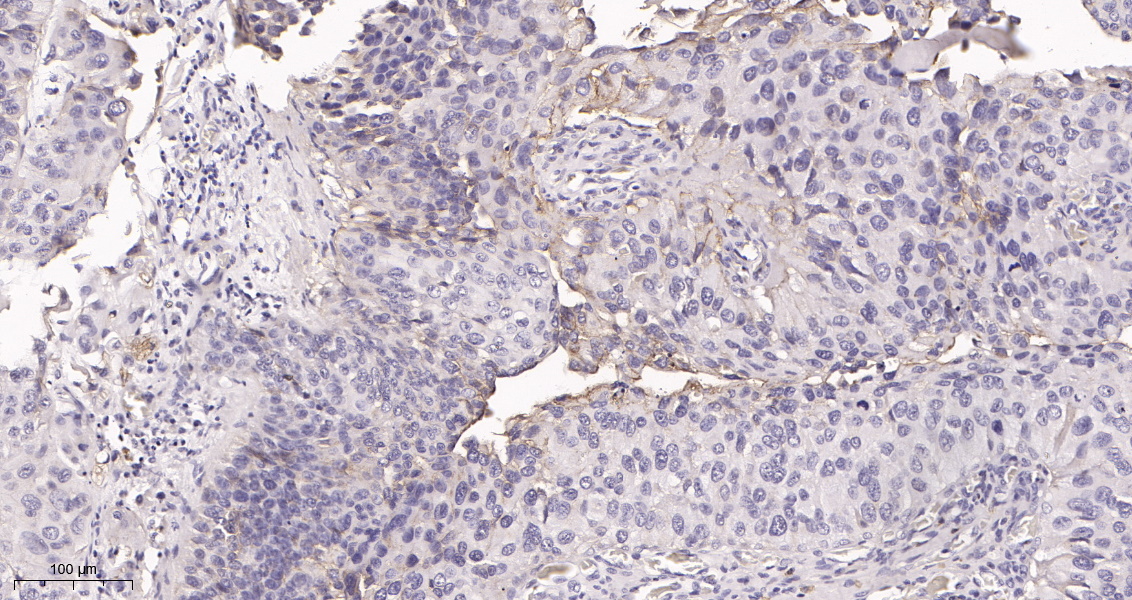

产品名称IGF1 Receptor (12N19) Rabbit Monoclonal Antibody

推荐应用WB,IHC-P,IF-P,IF-F,IF-ICC,ELISA

稀释度IHC-P 1:100-200, WB 1:1000-5000, IF-P/IF-F/IF-ICC 1:200-1000, ELISA 1:5000-20000

背景介绍This receptor binds insulin-like growth factor with a high affinity. It has tyrosine kinase activity. The insulin-like growth factor I receptor plays a critical role in transformation events. Cleavage of the precursor generates alpha and beta subunits. It is highly overexpressed in most malignant tissues where it functions as an anti-apoptotic agent by enhancing cell survival. Alternatively spliced transcript variants encoding distinct isoforms have been found for this gene. [provided by RefSeq, May 2014].